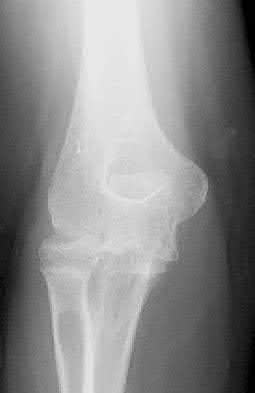

Figure A is an AP radiograph of a posterior knee dislocation. Figure B is a lateral showing the same injury.